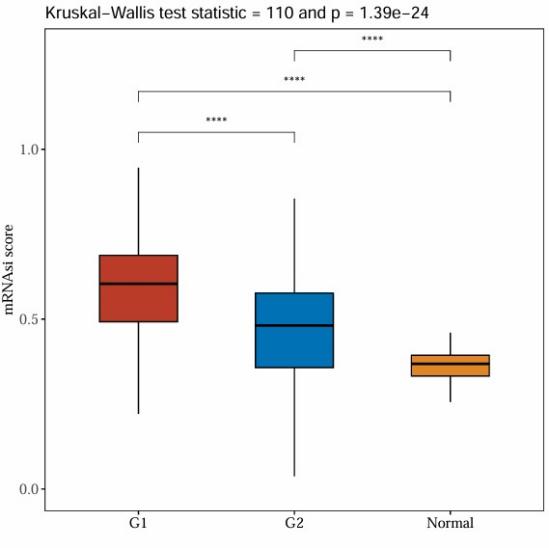

3.5. EZH2 expression and its role in tumor stemness

HCC patients were classified into high and low EZH2 expression groups to study the role of the key gene EZH2 in tumor stemness. There was a notable positive correlation between EZH2 expression and tumor stemness, according to Spearman correlation analysis (Figure 9). The correlation coefficient and p-value are displayed, indicating a strong association between EZH2 expression and stemness scores.